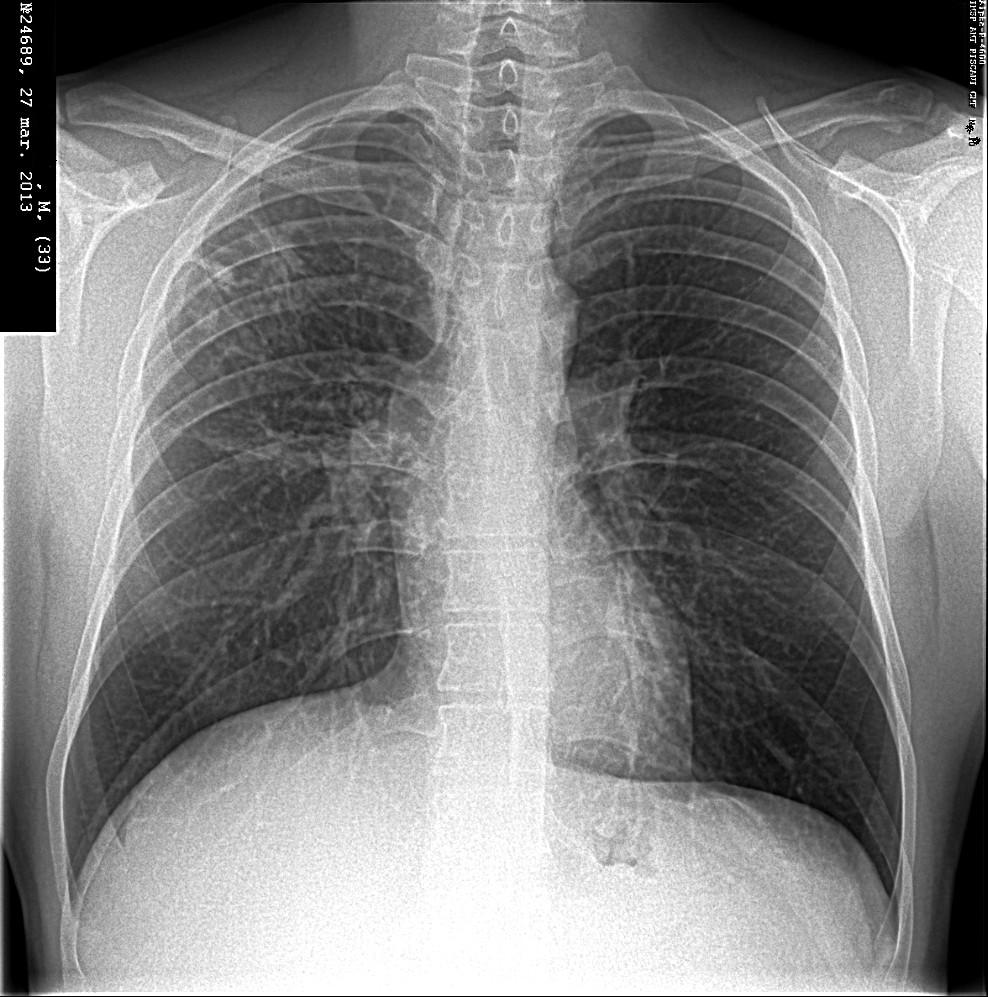

Симптомы и лечение инфильтративного туберкулеза легких

Раздел: Снимки-откровения